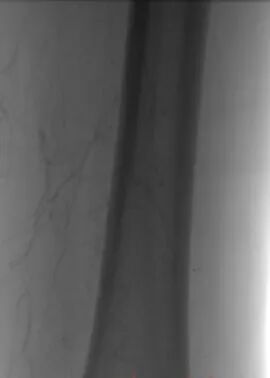

第一个病例中,患者因下肢严重缺血入院。术前常规血管造影提示为“动脉闭塞”。如果按照传统思路,需要直接实施球囊扩张加支架植入手术。为实现精准诊疗,血管外科团队决定启用IVUS进行血管腔内探查。

IVUS探头进入血管后,病变真相清晰呈现。血管内并非预想的慢性动脉硬化斑块,而是大块脱落的血栓堵塞了血管。患者属于急性或亚急性栓塞,与慢性闭塞的治疗方案截然不同,原本的支架方案必须推翻。